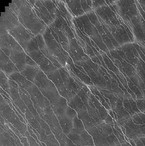

Moderne OCT-Geräte sind heute mit Zusatzmodulen ausrüstbar, die Schichtaufnahmen einzelner Netzhautebenen ermöglichen. Hierbei ist auch die Dynamik des retinalen Blutflusses darstellbar, was als OCT-Angiographie derzeit klinisch erprobt wird (Abb. 2). Die Aufnahmen sind hochauflösend und bieten detaillierte Einblicke in die Mikroarchitektur der Netzhaut und des Gefäßsystems. Dass hierbei kein Farbstoff appliziert werden muss, ist zwar für den Patienten sehr angenehm, andererseits kann aber mit dieser Methode weder eine Leckage noch eine Farbstoffansammlung (Pooling) dargestellt werden. Eine abschließende Bewertung der klinischen Bedeutung dieser Technik steht noch aus.